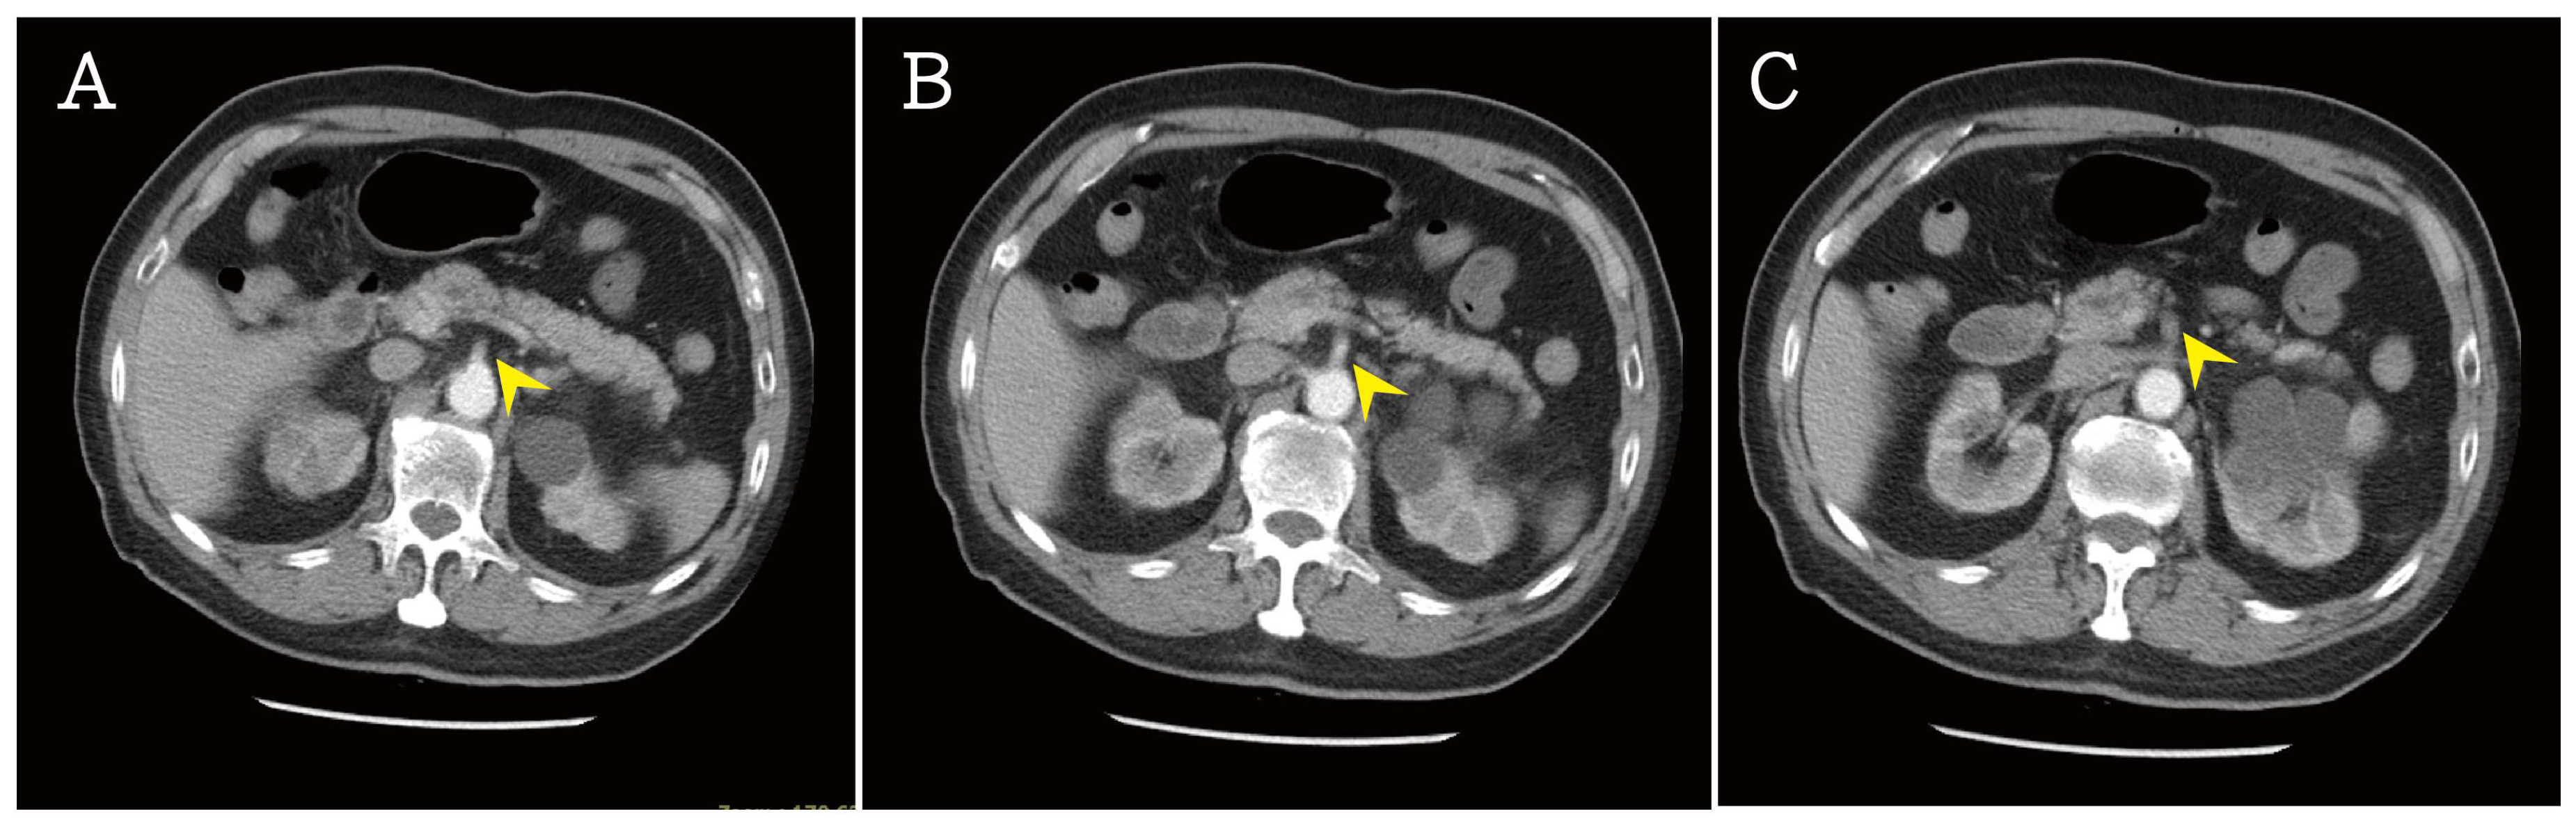

2. Case Presentation Section